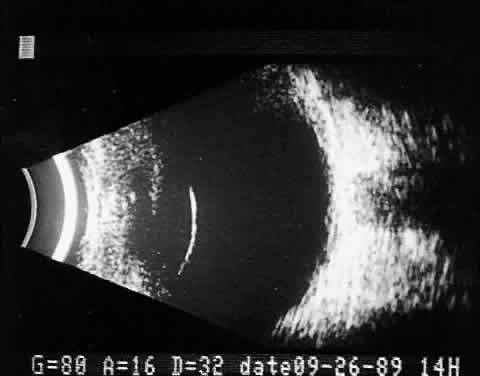

Fig. 11. Contact B-scan: malignant melanoma, demonstrating hollowing and choroidal excavation.